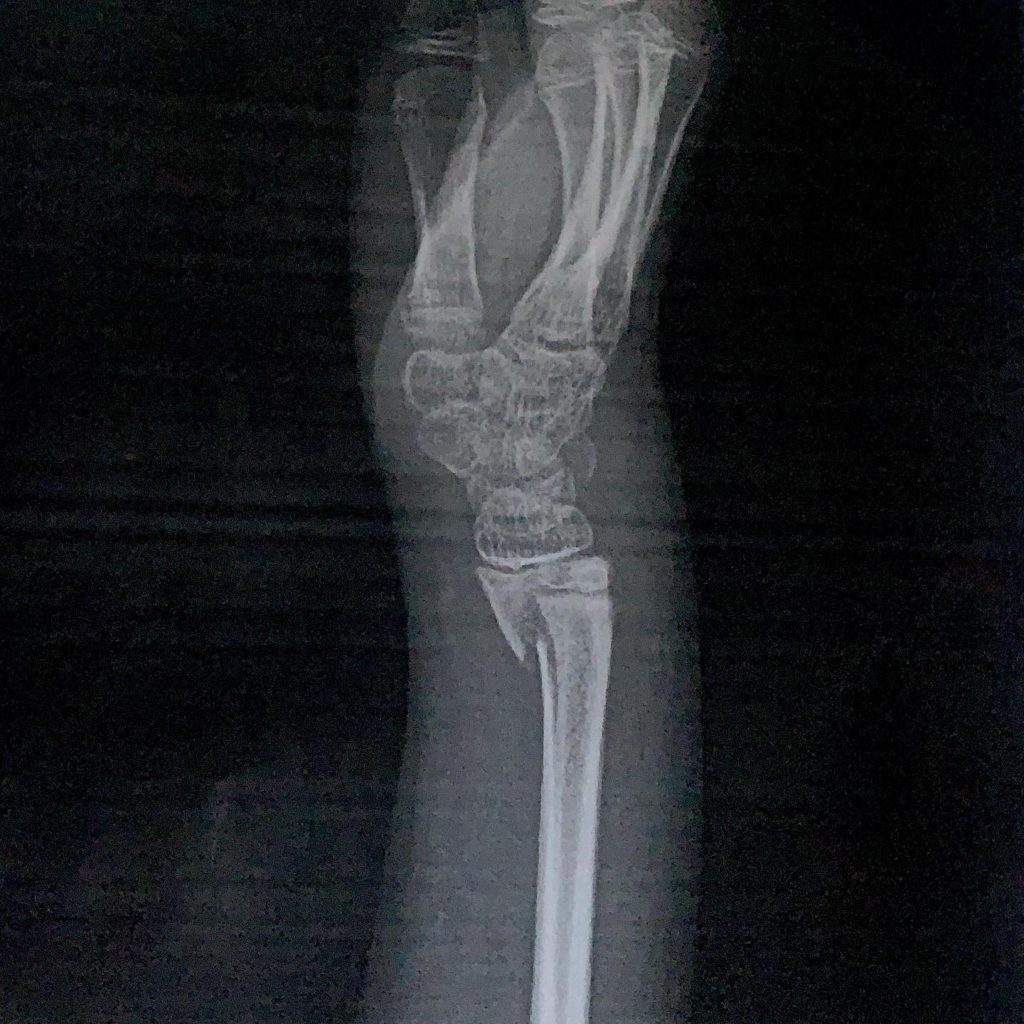

撤収間際に遊んでいて転けた次男が手首骨折😅💦

キャンプ場から自宅に帰る前に病院へ行き、骨折の処置をしてもらう。

私と同じ右手だよ🤣🤣🤣